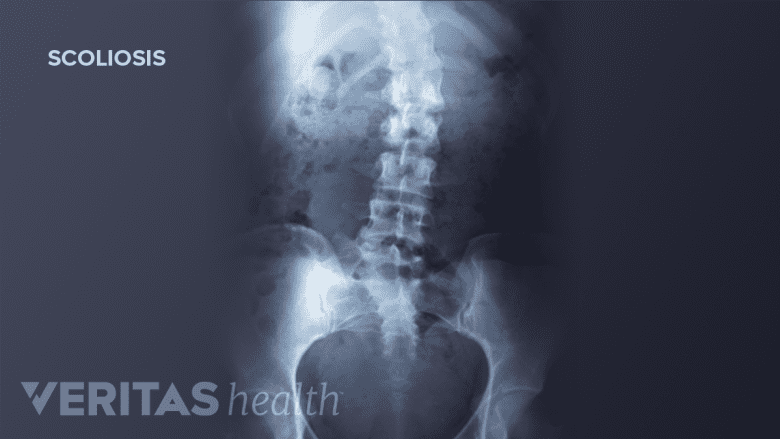

An official diagnosis of idiopathic scoliosis requires X-ray confirmation of the abnormal lateral curvature and spinal rotation, as well as ruling out other possible causes for the deformity (such as Scheuermann's disease, juvenile disc disorder, or ankylosing spondylitis).

The lateral curve of scoliosis is described by the Cobb angle. Using an X-ray of the full spine, the Cobb angle is found by drawing a perpendicular line from the spine’s most-tilted vertebra above the sideways curve’s apex and a second perpendicular line from the most-tilted vertebra beneath the apex. The angle formed where those two lines meet is the Cobb angle.

A Cobb angle of at least 10 degrees is typically considered the borderline for a scoliosis diagnosis.

- Lateral curvature. The lateral (sideways) curvature of the spine is measured by the Cobb angle. The bigger the Cobb angle, the greater the spinal deformity.

- Axial rotation. In addition to the sideways curvature, the spine abnormally rotates along the vertical axis. Spinal rotation can affect rib rotation, as well as curve rigidity.

- Skeletal maturity. Often estimated by the Risser sign (amount of calcification at the hip bone’s ridged top as seen on the same X-ray as the Cobb angle), the amount of skeletal maturity remaining is critical to making scoliosis treatment decisions in children and teens.